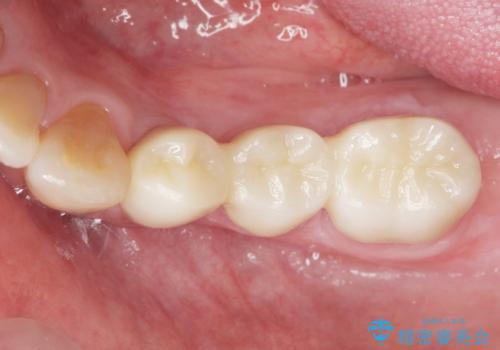

再生療法と骨外科処置により、歯周ポケットは全周2mm以下となりました。

根本的な歯周病の治療を行うことで不安がなくなり、患者様に喜んで頂けました。

また、奥歯の動揺がなくなりしっかりと咬むことができ、審美的・機能的にもご満足頂けました。

被せ物の種類:オールセラミッククラウン ベレッツァ